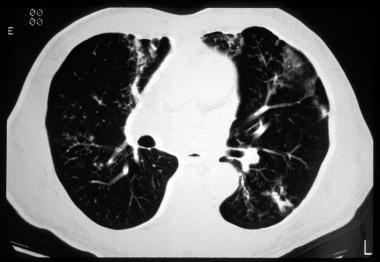

?空气潴留征:在呼气阶段获得的HRCT很容易发现空气潴留征 , 约81%的患者可发现过度充气 。

图6 左上叶的局部过度充气 , 且可见支气管壁增厚

?马赛克症是HRCT扫描中小气道异常的第二个征象 , 约64%的患者可见马赛克症 。

?支气管壁增厚 , 约48%-76%的患者可见支气管壁增厚 。

?支气管扩张:支气管扩张是最常见的CT异常 , 约80%的患者可见支气管扩张 , 可见柱状型、曲张型和囊状型扩张 。

图10 可见支气管周围的磨玻璃样浑浊及过度充气